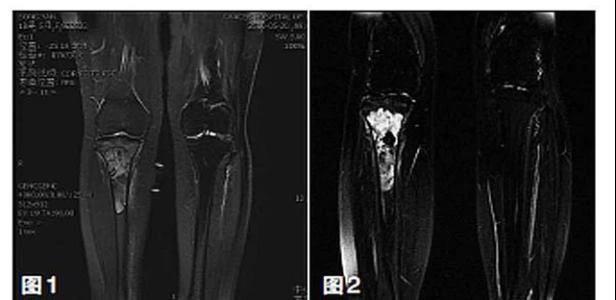

保肢治療指經(jīng)典型骨肉瘤在多學(xué)科團(tuán)隊(duì)醫(yī)生共同努力下完成的新輔助化療、保肢手術(shù)和輔助化療等一系列治療總稱,其目的是在提高患者生存率的前提下,減少局部復(fù)發(fā)、盡量保留良好的肢體功能。肢體經(jīng)典型骨肉瘤保肢治療方法如下圖所示:

新輔助化療的目的是盡早殺滅遠(yuǎn)處微小轉(zhuǎn)移灶,縮小腫瘤及周圍炎性水腫反應(yīng)區(qū),以利于后續(xù)的保肢手術(shù);觀察腫瘤對(duì)化療的敏感性,為進(jìn)一步指定個(gè)體化的術(shù)后化療方案奠定基礎(chǔ)。骨肉瘤新輔助化療下的保肢治療如下圖所示: